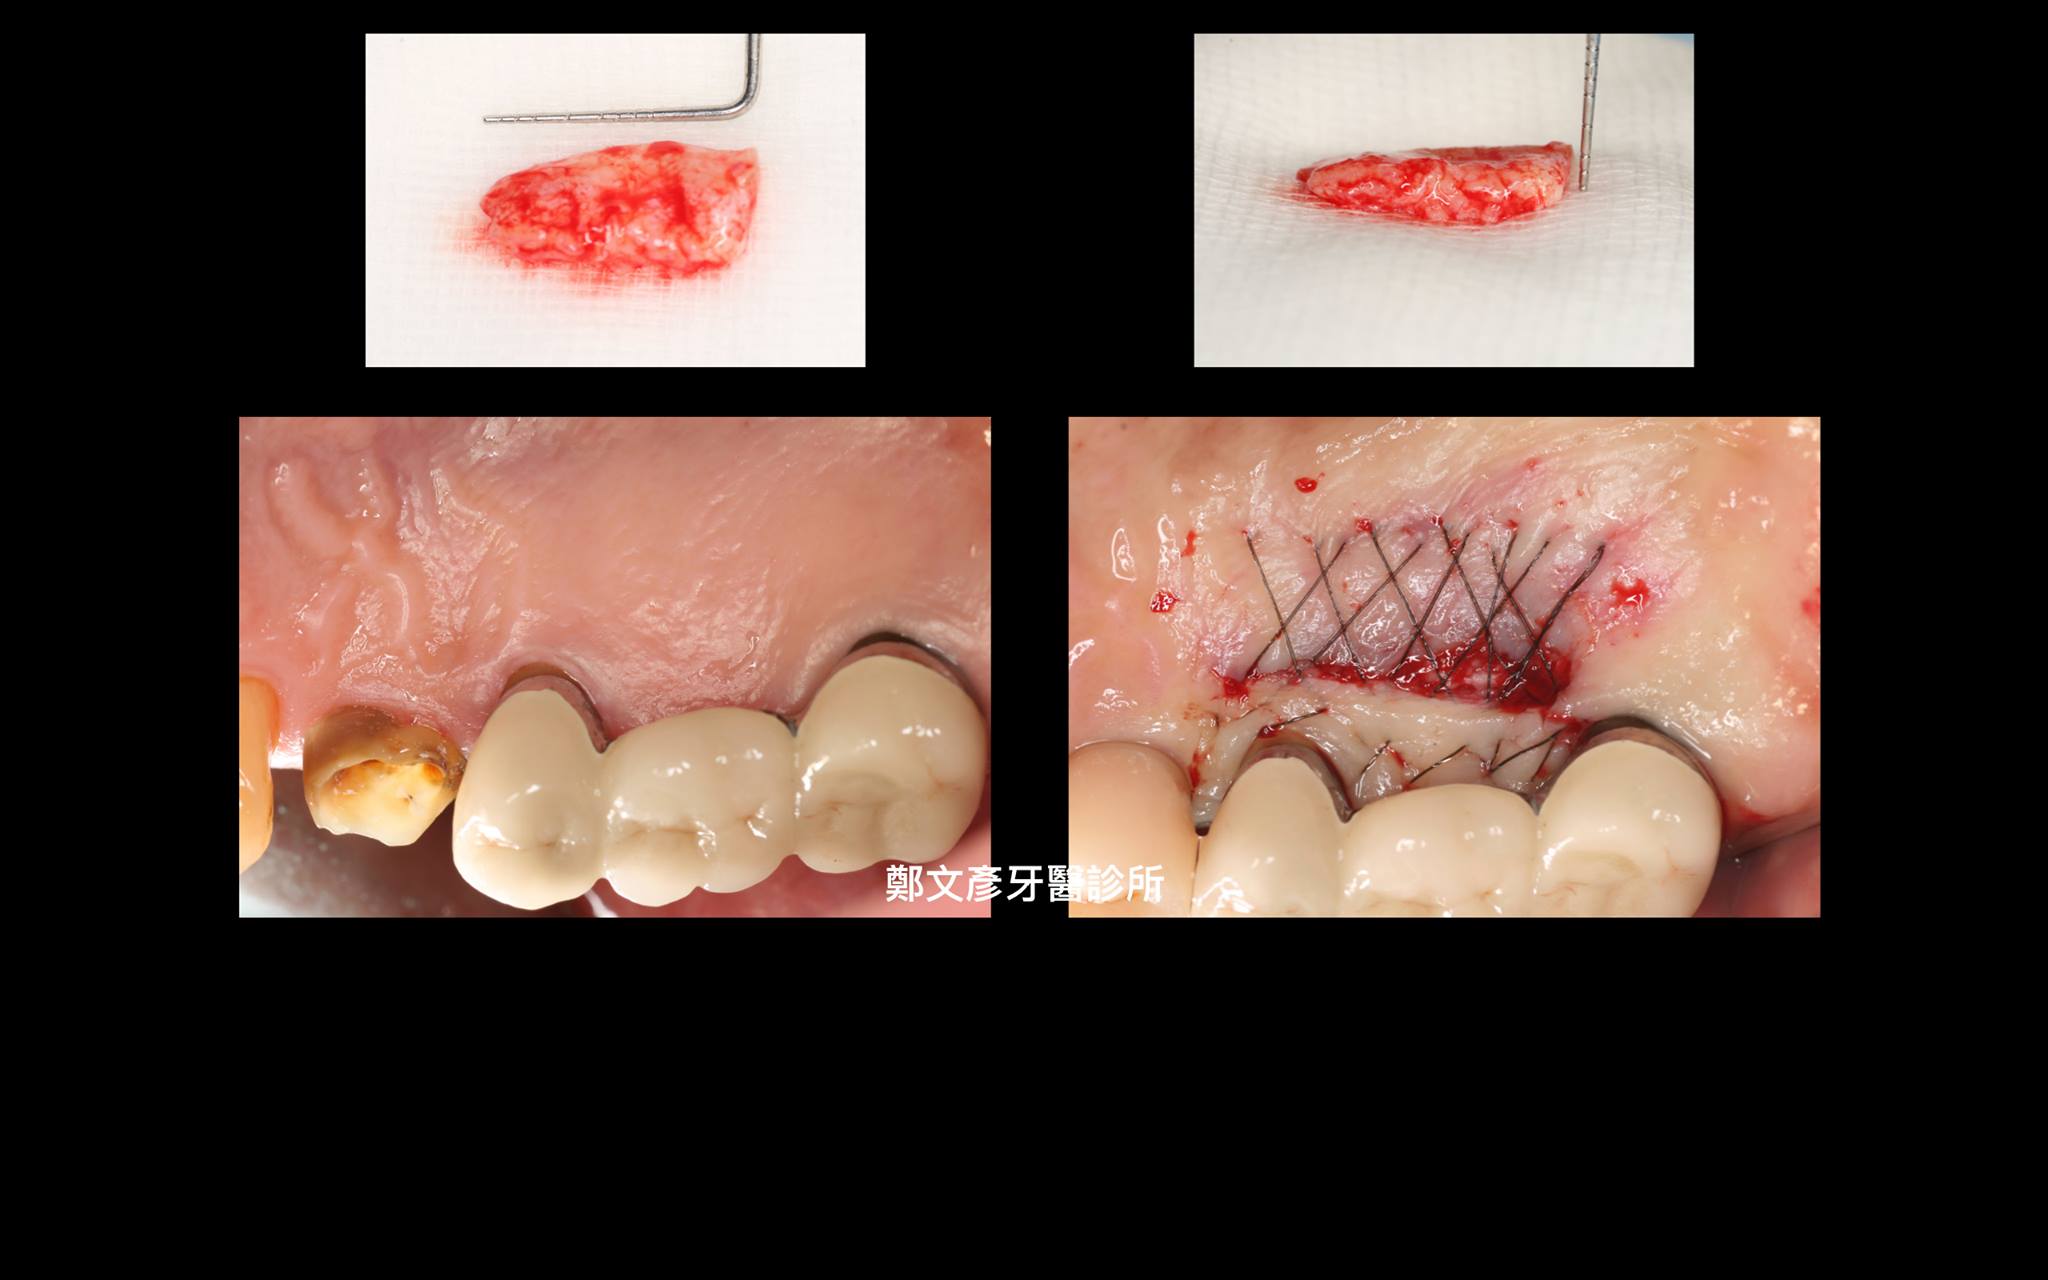

植牙美學(後牙區)

植牙美學